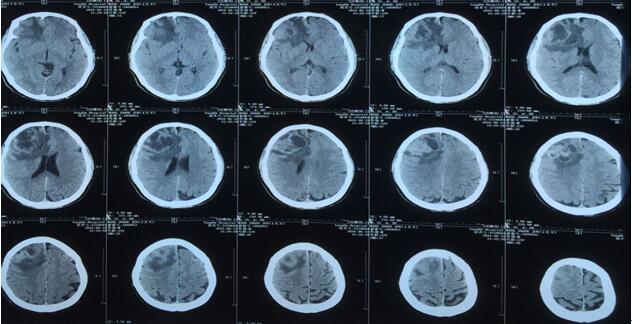

患者王某某,男,53歲,因“間斷頭痛半月”入神經(jīng)內(nèi)科十二病區(qū),發(fā)現(xiàn)顱內(nèi)占位后轉(zhuǎn)入神經(jīng)外科。既往患者有肺Ca病史,于一年前行手術(shù)治療。頭顱影像學(xué)診斷膠質(zhì)瘤?轉(zhuǎn)移瘤待排。2016年6月29日在3.0T磁共振定位后,劉增強副主任與其團隊為患者實施了立體定向腦內(nèi)病變活檢術(shù),此患者病灶為囊實性,手術(shù)難度較大,而一旦囊液流失則會發(fā)生腦組織漂移,導(dǎo)致靶點移位,因此手術(shù)計劃制定尤為重要,入顱點為右額部,穿刺后首先達到腫瘤實性部分,獲取病灶標本后,抽出部分囊液以緩解患者高顱壓癥狀,經(jīng)過精細的手術(shù)操作,最終成功獲取腫瘤標本,并且抽出約20ml腫瘤液,患者情況穩(wěn)定,術(shù)后兩小時即下床活動。

術(shù)后冰凍切片報告考慮轉(zhuǎn)移瘤,我院石蠟病理結(jié)果為少許低分化癌組織,結(jié)合病史符合肺癌腦轉(zhuǎn)移。